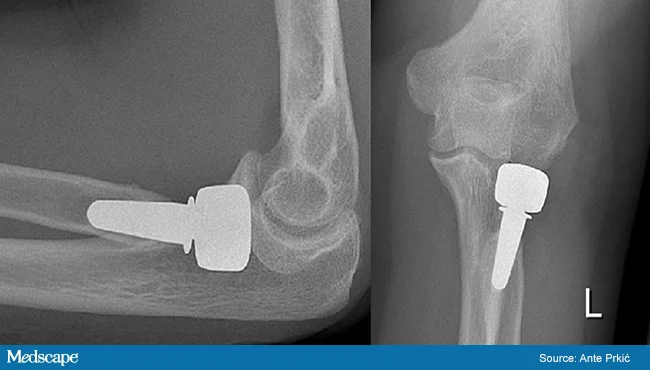

- Radial head Replacement if comminuted /inoperable